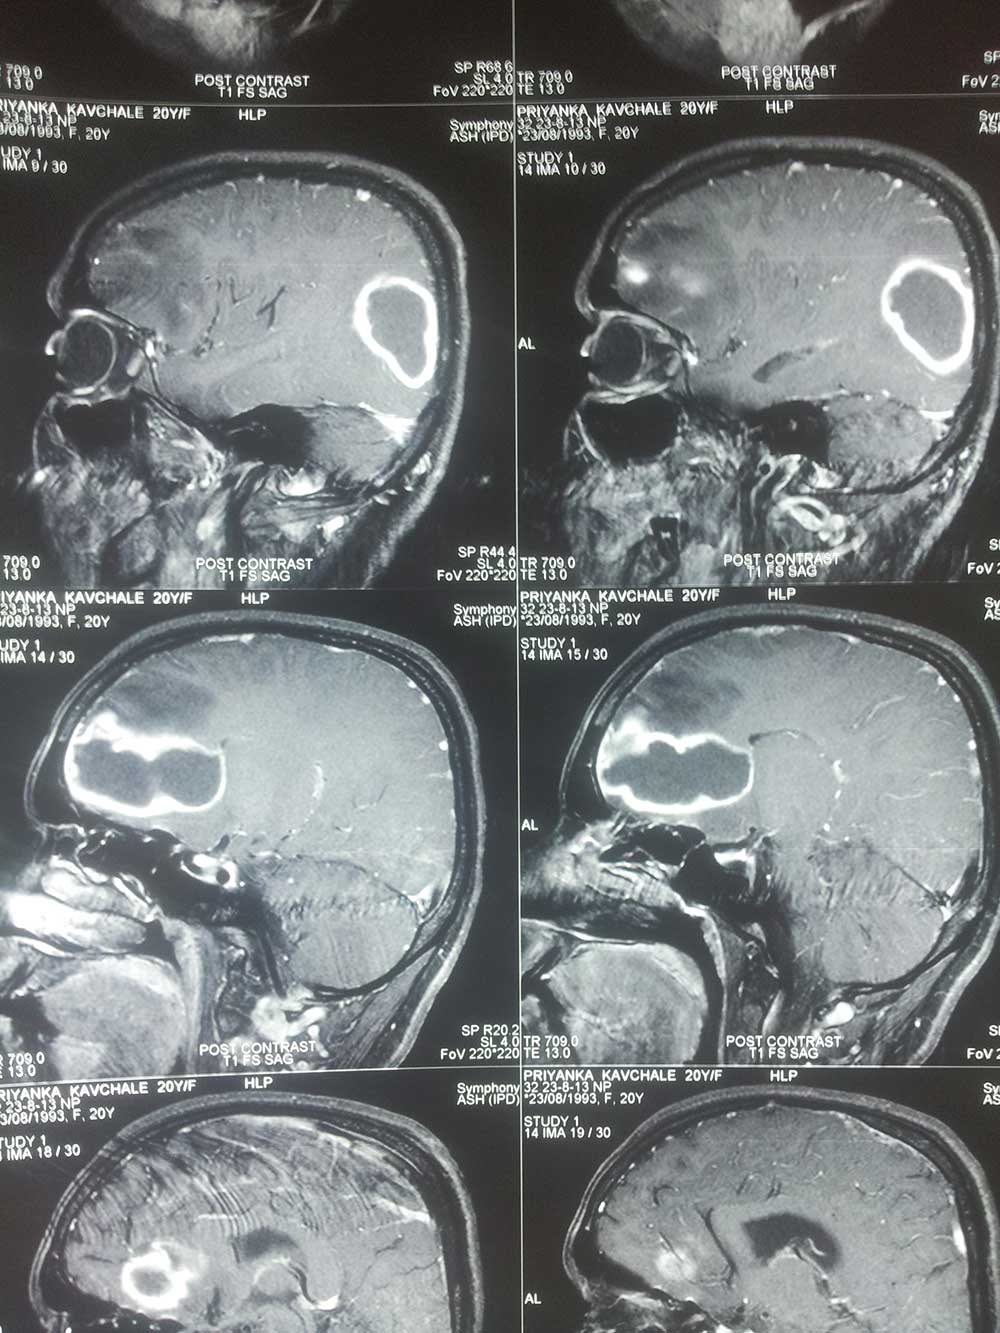

Brain Abscess Brain Abscess Post OP 2 Clinical Intra OP ,After Excising The Granuloma Intaop Scalp Abscess CT Scalp Abscess Cerebellar Abscess Post OP Clinical Cerebellar Abscess Brain TB Granuloma Post OP CT Scan Brain Infection Brain Abscess Preop MRI 2 Brain Abscess PRE OP Clinical 1 Brain Abscess PRE OP Brain Abscess Intraop 2 Brain Abscess Following Shunt Temporal Abscess T2W of TB Granuloma Scalp Abscess Preop CT Marking PRW OP MRI of TB Granuloma Post OP Clinical Photo Post OP Cerebellar Abscess Post OP Brain Abscess Intraop Specimen of Granuloma